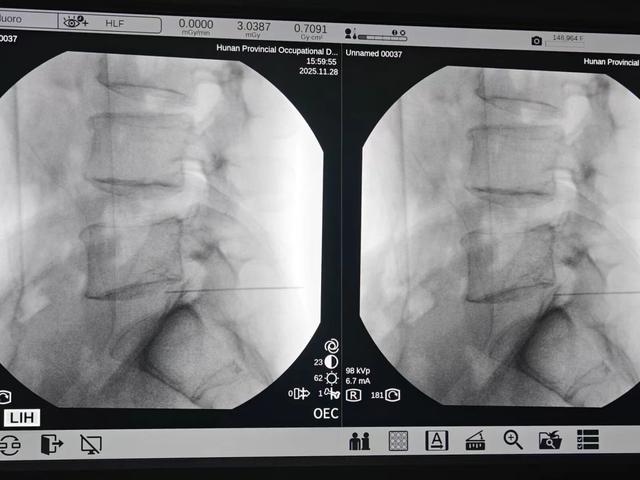

手术在C型臂X光或CT的实时引导下进行,医生能将穿刺误差控制在 1毫米 以内,像“制导导弹”一样精准命中突出的髓核组织,完全避开正常的神经与脊柱结构,避免了传统手术对脊柱稳定性的影响。